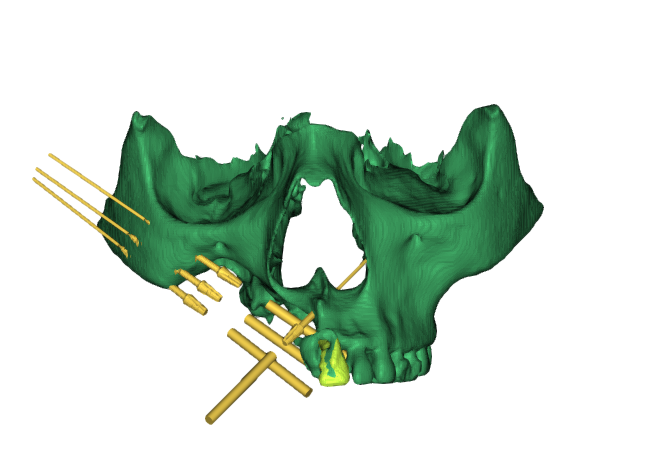

To tackle the complexity, the decision was made to create a 3D-printed maxillary model. This model, based on the patient’s CT scan, served as an exact replica of the residual bone and defect. The oral surgeon then performed a mock surgery on the printed model to assess:

- Feasibility of implant placement.

- Strength and suitability of anatomical areas.

- Possible complications during actual surgery.

The mock surgery revealed key findings:

- Placement of three zygomatic implants was possible — something rarely attempted and only confirmed during the model-based rehearsal.

- A single conventional implant could be placed in the incisor region.

- Pterygoid implants were ruled out due to weak bone and lack of tuberosity support.